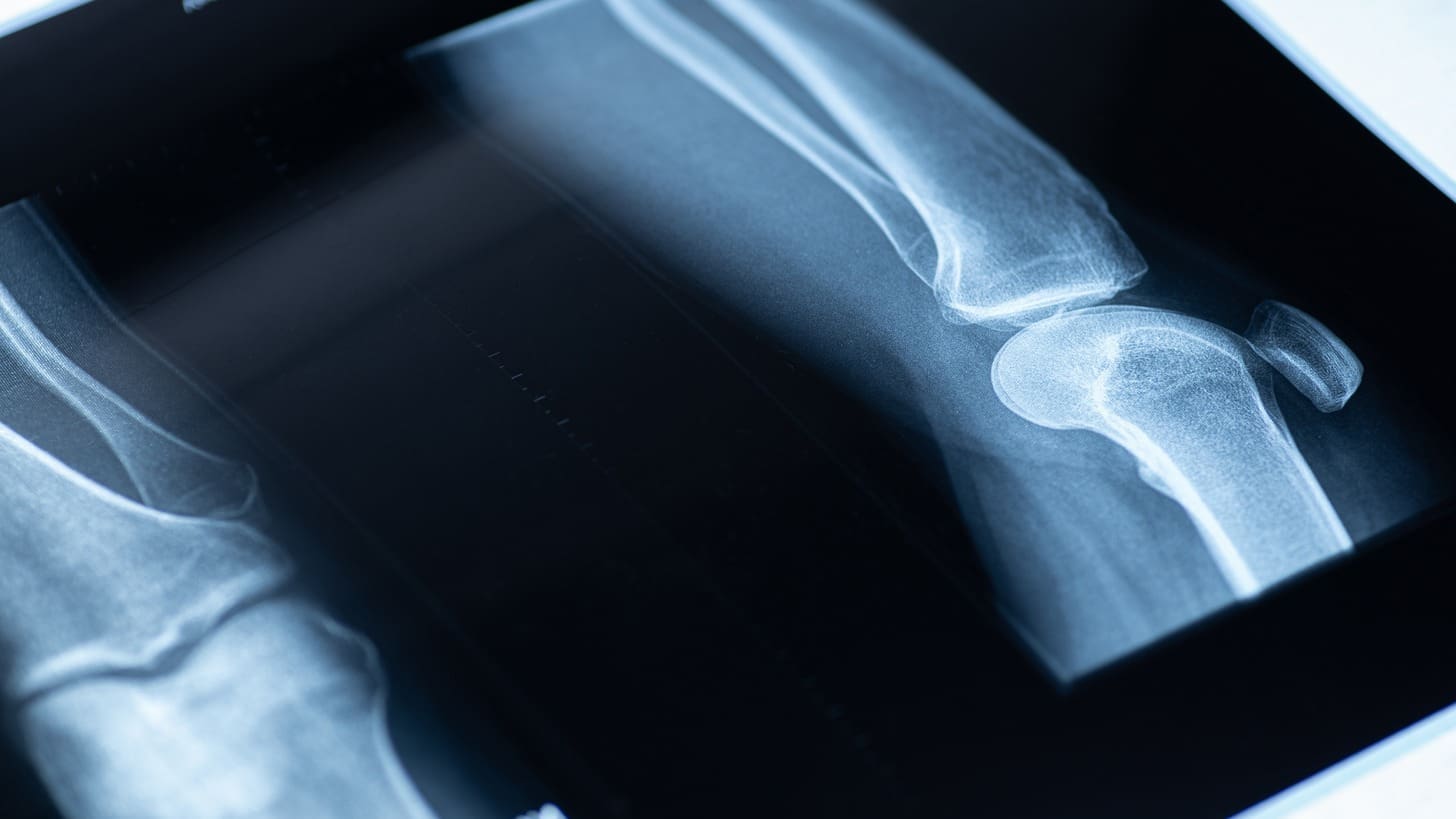

Gamma imaging works by detecting gamma radiation from radiopharmaceuticals in the body. It’s a way to see how certain diseases or conditions work. This method is also known as nuclear medicine.

Gamma rays start when a special medicine is given to a patient. This medicine goes to the area we want to see. A gamma camera then picks up these rays.

The camera uses a special part to focus the rays. When these rays hit a crystal, it lights up. This light is turned into an electrical signal. This signal helps make images of what’s inside the body.

Medical Applications of Gamma Imaging

We use gamma imaging in many medical fields to improve diagnosis and treatment. It’s a key tool in healthcare today, giving us vital info about the body’s inner workings.

Diagnostic Uses Across Medical Specialties

Gamma imaging is vital in oncology, cardiology, and neurology. It spots and stages cancers in oncology. In cardiology, it checks heart health and finds heart disease. Neurology uses it to diagnose brain issues and check blood flow.